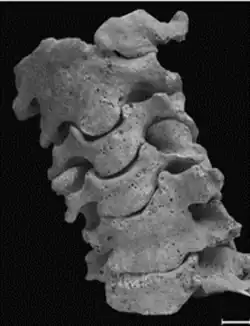

Num segundo caso, descrito por Fernandes e Costa (2007)[4], temos o esqueleto de um individuo de sexo masculino, com cerca de 40 anos de um cemitério medieval em Estremoz, datado do período entre o século XIII e XV. Este individuo tem uma vertebra cervical supranumerária, sendo a C0 uma hemivertebra (lado esquerdo) fundida ao côndilo occipital.

Quanto ao atlas (C1), não está fundido em plano sagital, sendo composto por duas hemivertebras. A hemivertebra direita está fundida com o áxis (C2) enquanto a esquerda não, articulando normalmente (figura 3). Neste par de vertebras a união é completa nos corpos vertebrais e facetas articulares, havendo desenvolvimento de uma ponte óssea entre os arcos. Consequente desta fusão, o áxis apresenta deformações no processo odontóide.

Mais abaixo, a C5 e C6 também estão fundidas (figura 3), tendo uma forma de cunha, que podem sugerir fraturas por compressão (importante no diagnostico diferencial). Aqui existe a união dos corpos vertebrais, e das facetas e arcos direitos, no entanto têm o processo transverso esquerdo independente.

Para alem destas duas fusões, este individuo tem também outras anomalias que estão associadas a um mau desenvolvimento da coluna vertebral. Tem 8 vertebras cervicais, 11 torácicas, 6 lombares e 5 sacrais; uma costela cervical fundida ao processo transverso da C7; fenda no processo espinhoso da T3; leve assimetria na dimensão dos braços; escoliose cervical (figura 3); e diferença na elevação das escapulas (Fernandes e Costa, 2007)[4], que pode sugerir a deformidade de Sprengel. Estas alterações enquadram-se com a síndrome de Klippel-Feil de tipo II.